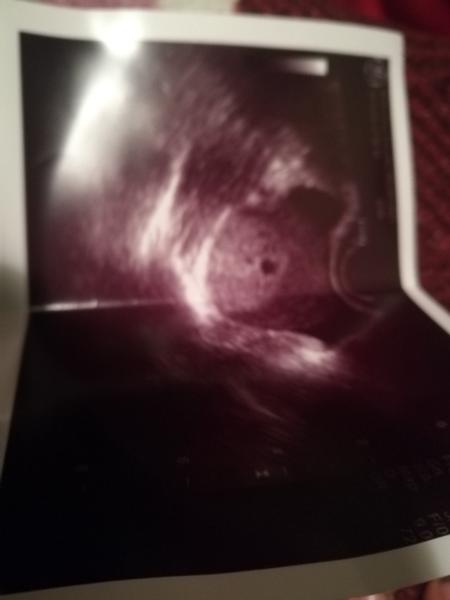

@maminka2020 muj utz 5+3 nevidela jsem skoro nic 😅

@maminka2020 mam stejnou fotku, bublinku jsem sice mela, ale malo viditelnou, skoro zadnou, taky jsem byla 6+1, srdicko jsem videla az za tyden a pul.

@maminka2020 Mám z 6+2